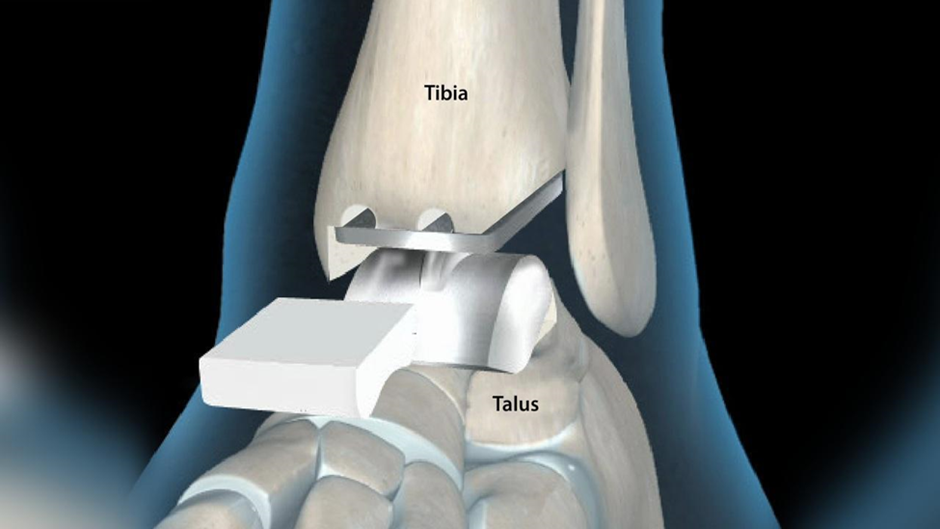

Your orthopedic surgeon removes the ankle joint and replaces it with an artificial ankle during the total ankle replacement surgery. This artificial implant is usually made of plastic and metal. The main idea behind ankle replacement is to use artificial implants to reduce pain and preserve ankle motion. In simple terms, this medical procedure aims at relieving your pain and promoting better function of your ankle when performing various activities.